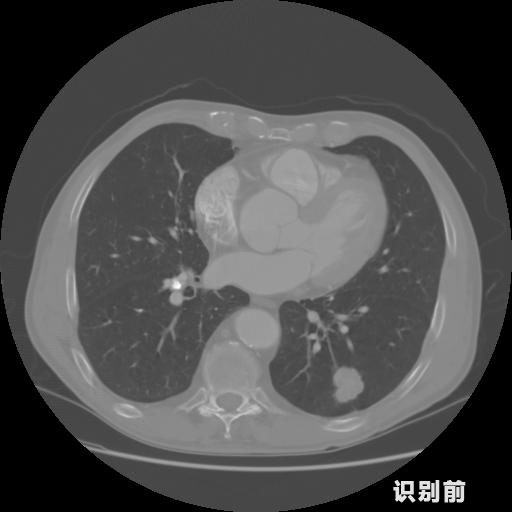

英特健康AI深度學習醫(yī)療圖像識別系統(tǒng)案例_胸部CT